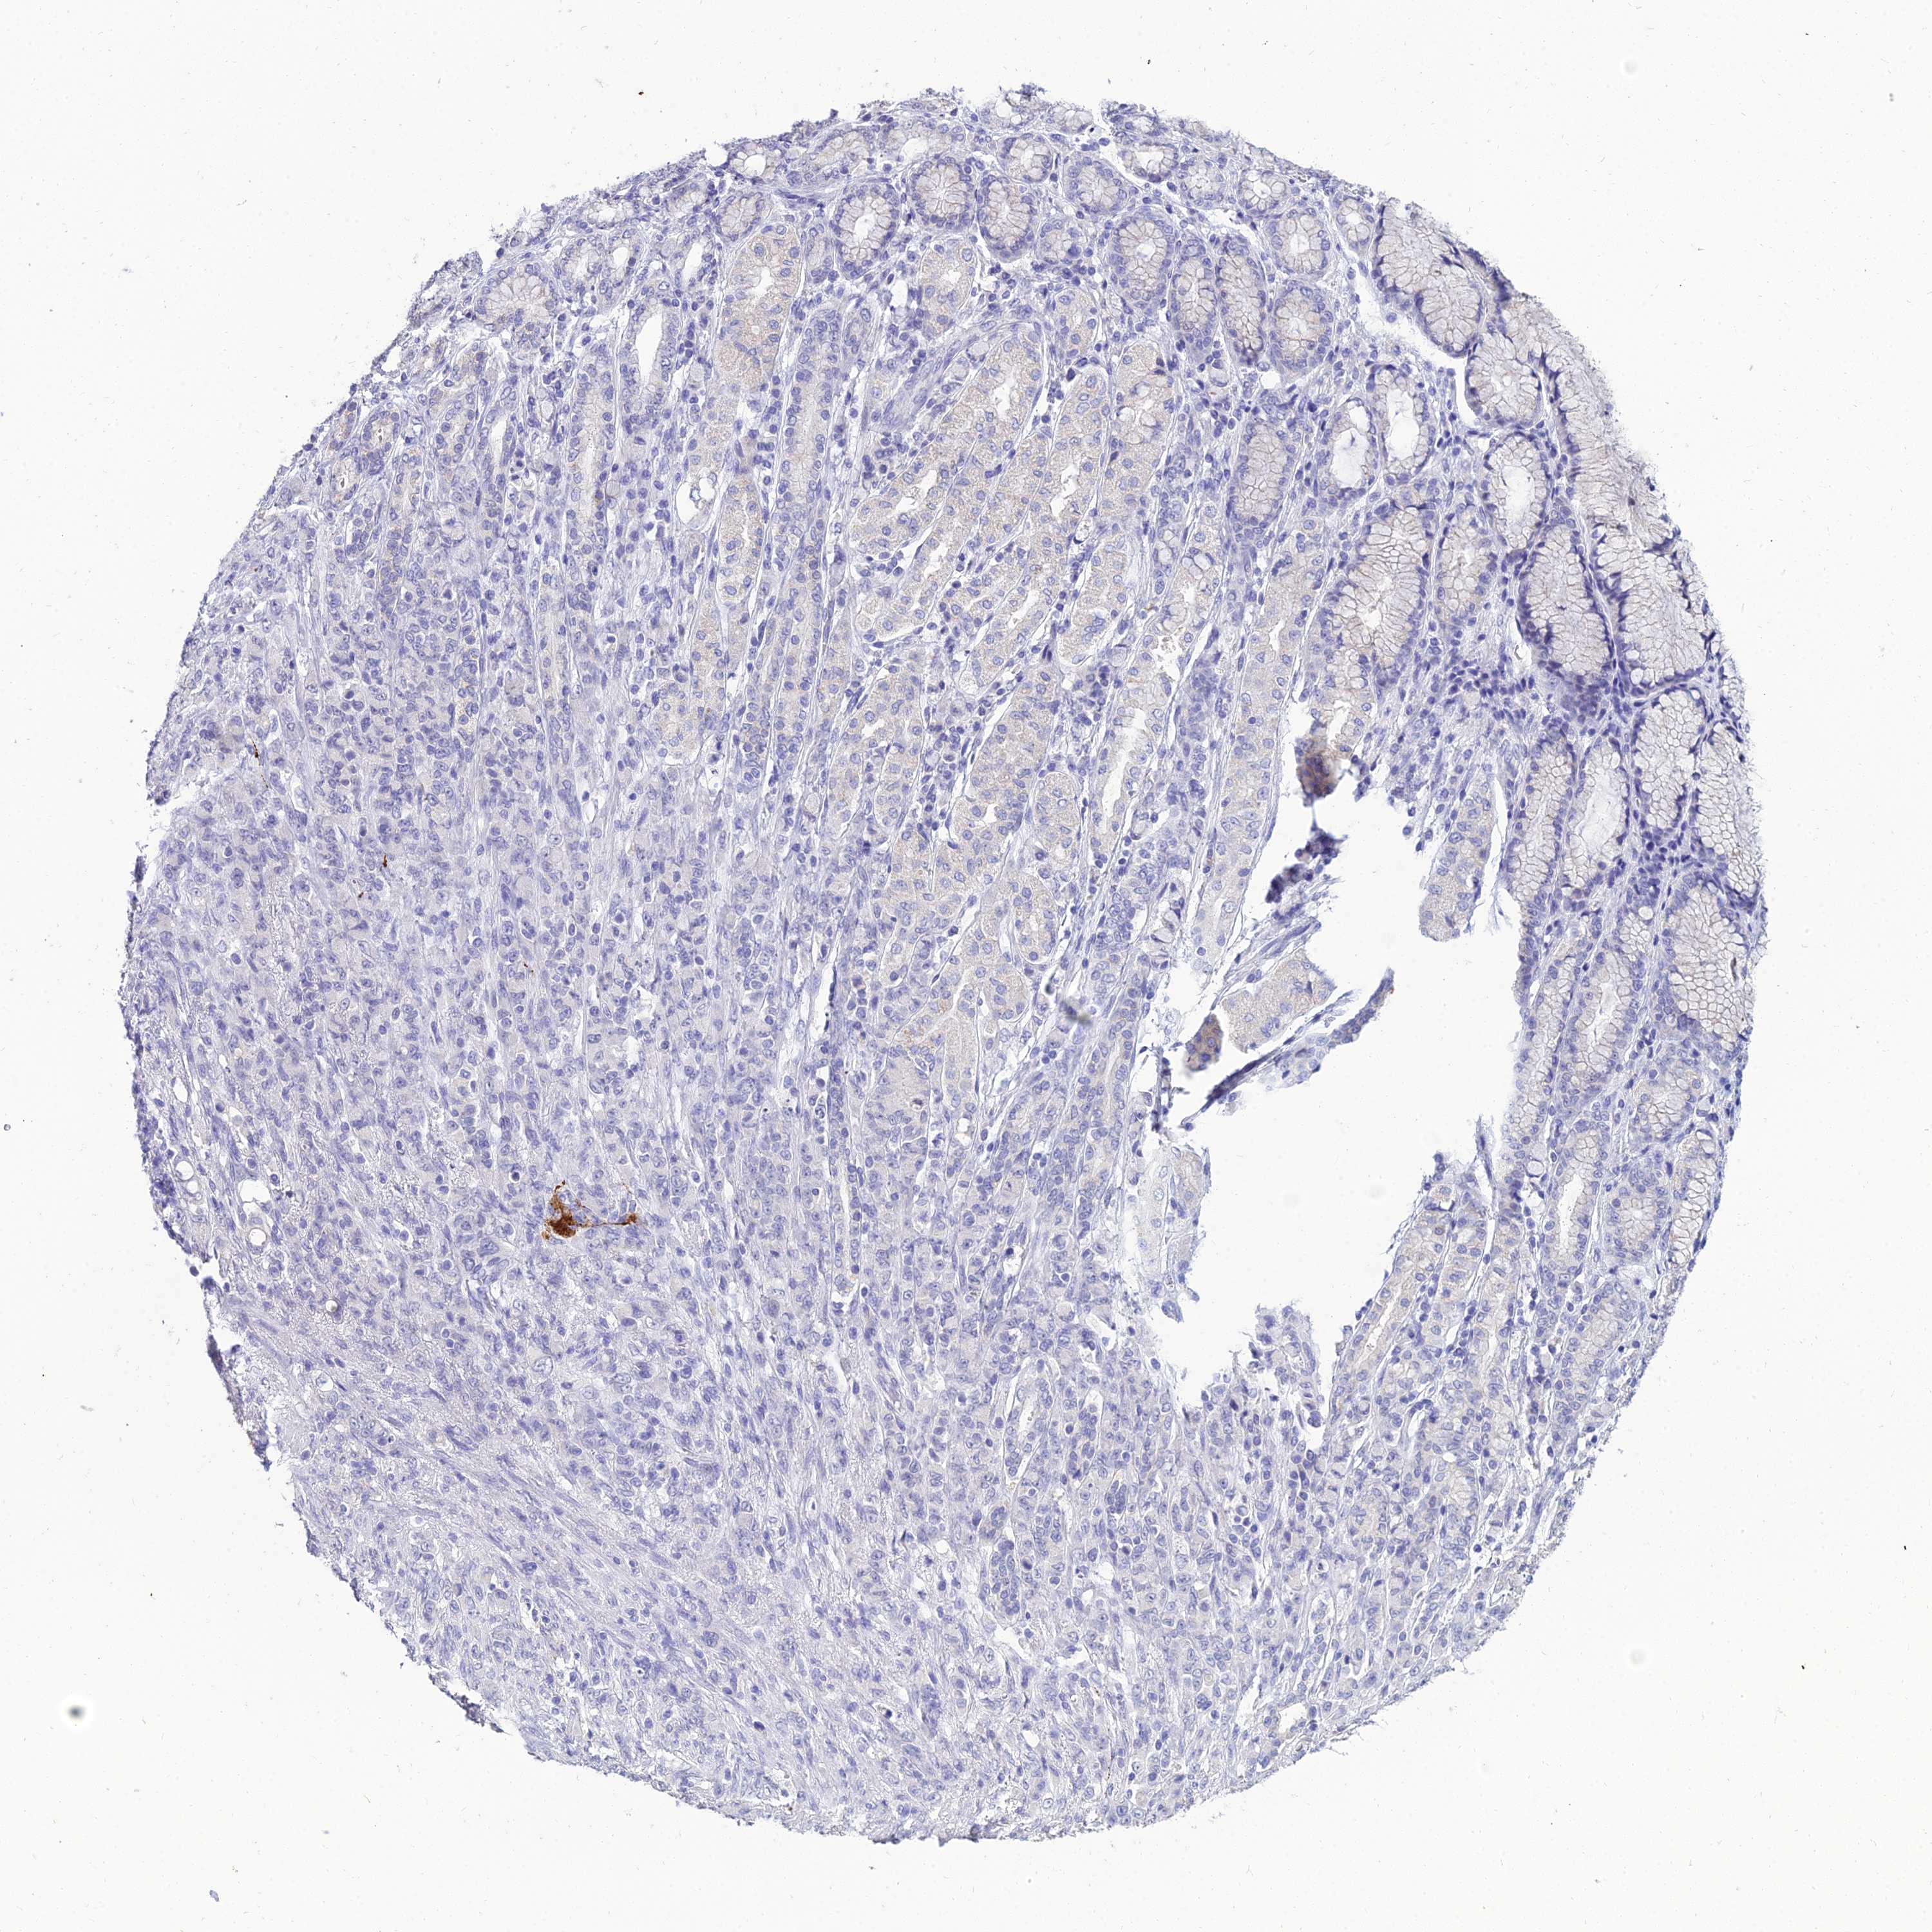

STOMACH CANCER - Protein expressioni

A mouse-over function shows sample information and annotation data. Click on an image to view it in a full screen mode. Samples can be filtered based on level of antibody staining by selecting one or several of the following categories: high, medium, low and not detected. The assay and annotation is described here.

Antibody stainingi

Antibody staining in the annotated cell types in the current human tissue is reported as not detected, low, medium, or high, based on conventional immunohistochemistry profiling in selected tissues. This score is based on the combination of the staining intensity and fraction of stained cells.

Each image is clickable and will lead to virtual microscopy that enables deeper exploration of all samples and also displays staining intensity scores, fraction scores and subcellular localization as well as patient and tissue information for each sample.

Antibody HPA044572

Antibody HPA056798

Antibody CAB016733

Antibody CAB034368

Staining

High

Medium

Low

Not detected

Intensity

Strong

Moderate

Weak

Negative

Quantity

>75%

75%-25%

<25%

None

Location

Nuclear

Cytoplasmic/membranous

Cytoplasmic/membranous,nuclear

Adenocarcinoma, NOS